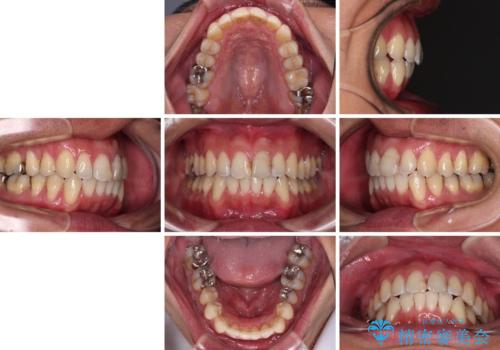

ワイヤー装置をインビザラインへ 装置変更での矯正治療

- 1年2ヶ月

- 治療費の目安: 135万円(税込) (当初予定では90万円)費用は治療当時の料金となります